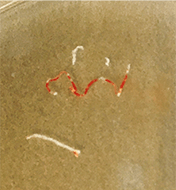

CTで膵頭部腫瘤を指摘

EUS-FNAで組織採取

採取された検体

膵癌と診断